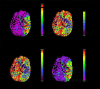

BACKGROUND Coronavirus disease 2019 (COVID-19) caused by severe acute respiratory syndrome coronavirus 2 (SARS-CoV-2) primarily affects the lungs but can involve any organ. The medical community is struggling to cope with the critical illness associated with the disease. On top of that, patients who have recovered from COVID-19 have presented with complications such as thrombotic episodes in various organs both during and after being infected with SARS-CoV-2. A COVID-19-associated prothrombotic state has been mentioned in multiple recent research articles. The role of anticoagulants is debatable, because even after receiving them prophylactically, many patients have experienced thrombotic episodes. The situation, therefore, represents a challenge to the medical community. CASE REPORT We report on a COVID-19-associated prothrombotic state in a 65-year-old man with no history of comorbid illness. Initially, he presented with right-sided weakness and was found to have had an acute ischemic stroke. Urgent imaging after the stroke revealed changes on electrocardiography that were remarkable for left bundle branch block. The patient's elevated cardiac enzyme levels correlated with a silent acute myocardial infarction (MI). His echocardiogram revealed a left ventricular (LV) thrombus. He was managed with a multidisciplinary approach involving Neurology, Cardiology, and Medicine. CONCLUSIONS COVID-19-associated prothrombotic episodes involving arterial and venous systems have been reported in the literature. But concomitant stroke, acute MI, and LV thrombus rarely have been documented. The role of prophylactic or therapeutic anticoagulation is still unclear because even when patients are on these drugs, they continue to develop thrombotic episodes. Indeed, further studies are required to develop a standard management plan for what can be a fatal situation.